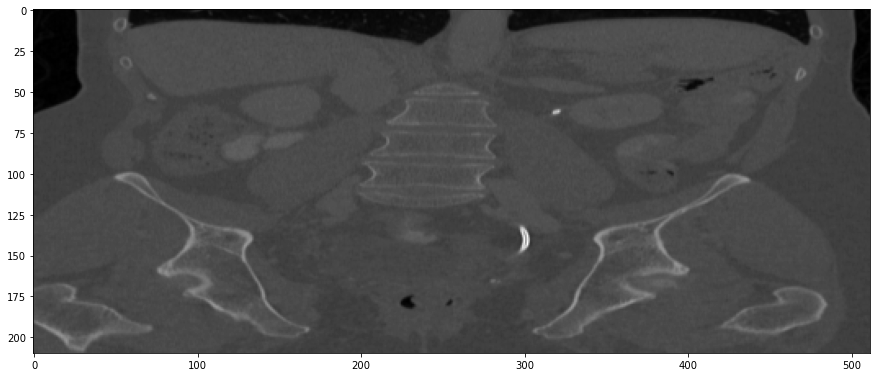

The results from all conducted experiments, represented as mean ±plus-or-minus\pm standard deviation, are tabulated in this section. We assessed the performance of our proposed simulation method against Simple Averaging, Gaussian Averaging, and Direct Downsampling. This was accomplished by simulating images with a thickness of 3mm from those with a thickness of 1mm, utilizing the 2016 Low Dose CT Grand Challenge dataset. The results outlined in Table III provide a comparative analysis of different thick-slice simulation methods used in two datasets from the 2016 Low Dose CT Grand Challenge. Both the PSNR and the RMSE were used as key performance indicators for these methods. The data clearly demonstrate that the proposed method significantly outperformed Simple Averaging, Gaussian Averaging, and Direct Downsampling in both datasets (D45 and B30). The highest PSNR values were obtained with the proposed method, yielding 49.7369 ±plus-or-minus\pm 2.5223 and 48.5801 ±plus-or-minus\pm 7.3271 for D45 and B30 datasets, respectively. The proposed method also registered the lowest RMSE with values of 0.0068 ±plus-or-minus\pm 0.0020 and 0.0108 ±plus-or-minus\pm 0.0099 for D45 and B30, respectively. These results indicate a superior level of accuracy and reliability in the proposed method. The statistically significant differences were confirmed by a Wilcoxon signed-rank test with p-value ¡ 0.05, implying that the improvements from the proposed method were not due to random chance. These findings support our first hypothesis that the proposed simulation method provides a more efficient and precise approach to thick-slice simulations compared to traditional methods. To provide a more comprehensive evaluation, visual comparisons from axial, coronal and sagittal plane were also undertaken, as depicted in Figures 2 to 4. In summary, Our proposed method demonstrated substantial enhancements in terms of both PSNR and RMSE, indicating a distribution more closely aligned with the authentic thick-slice image.

Refer to caption

(a) True Thick-slice image

(b) Simple Averaging

RMSE: 0.0357, PSNR: 34.9781

(c) Gaussian Averaging

RMSE: 0.0454, PSNR: 32.8866

(d) Direct Downsampling

RMSE: 0.0486, PSNR: 32.2861

(e) Proposed Simulation

RMSE: 0.0070, PSNR: 49.1774

Figure 4: Sagittal-plane thick-slice image quality comparison across four simulation methods.